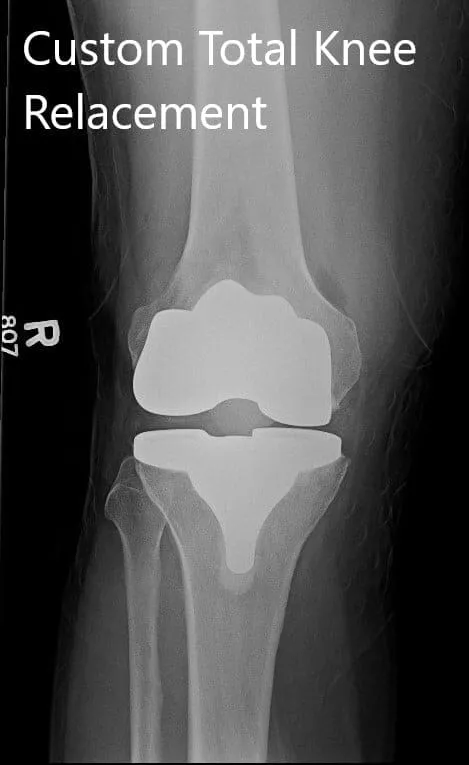

IMPLANTES UTILIZADOS: Fémur personalizado con tibia personalizada con inserto de polietileno de 10 mm y rótula de 32 mm x 6 mm.

Radiografía postoperatoria que muestra imágenes AP e laterales de la rodilla derecha